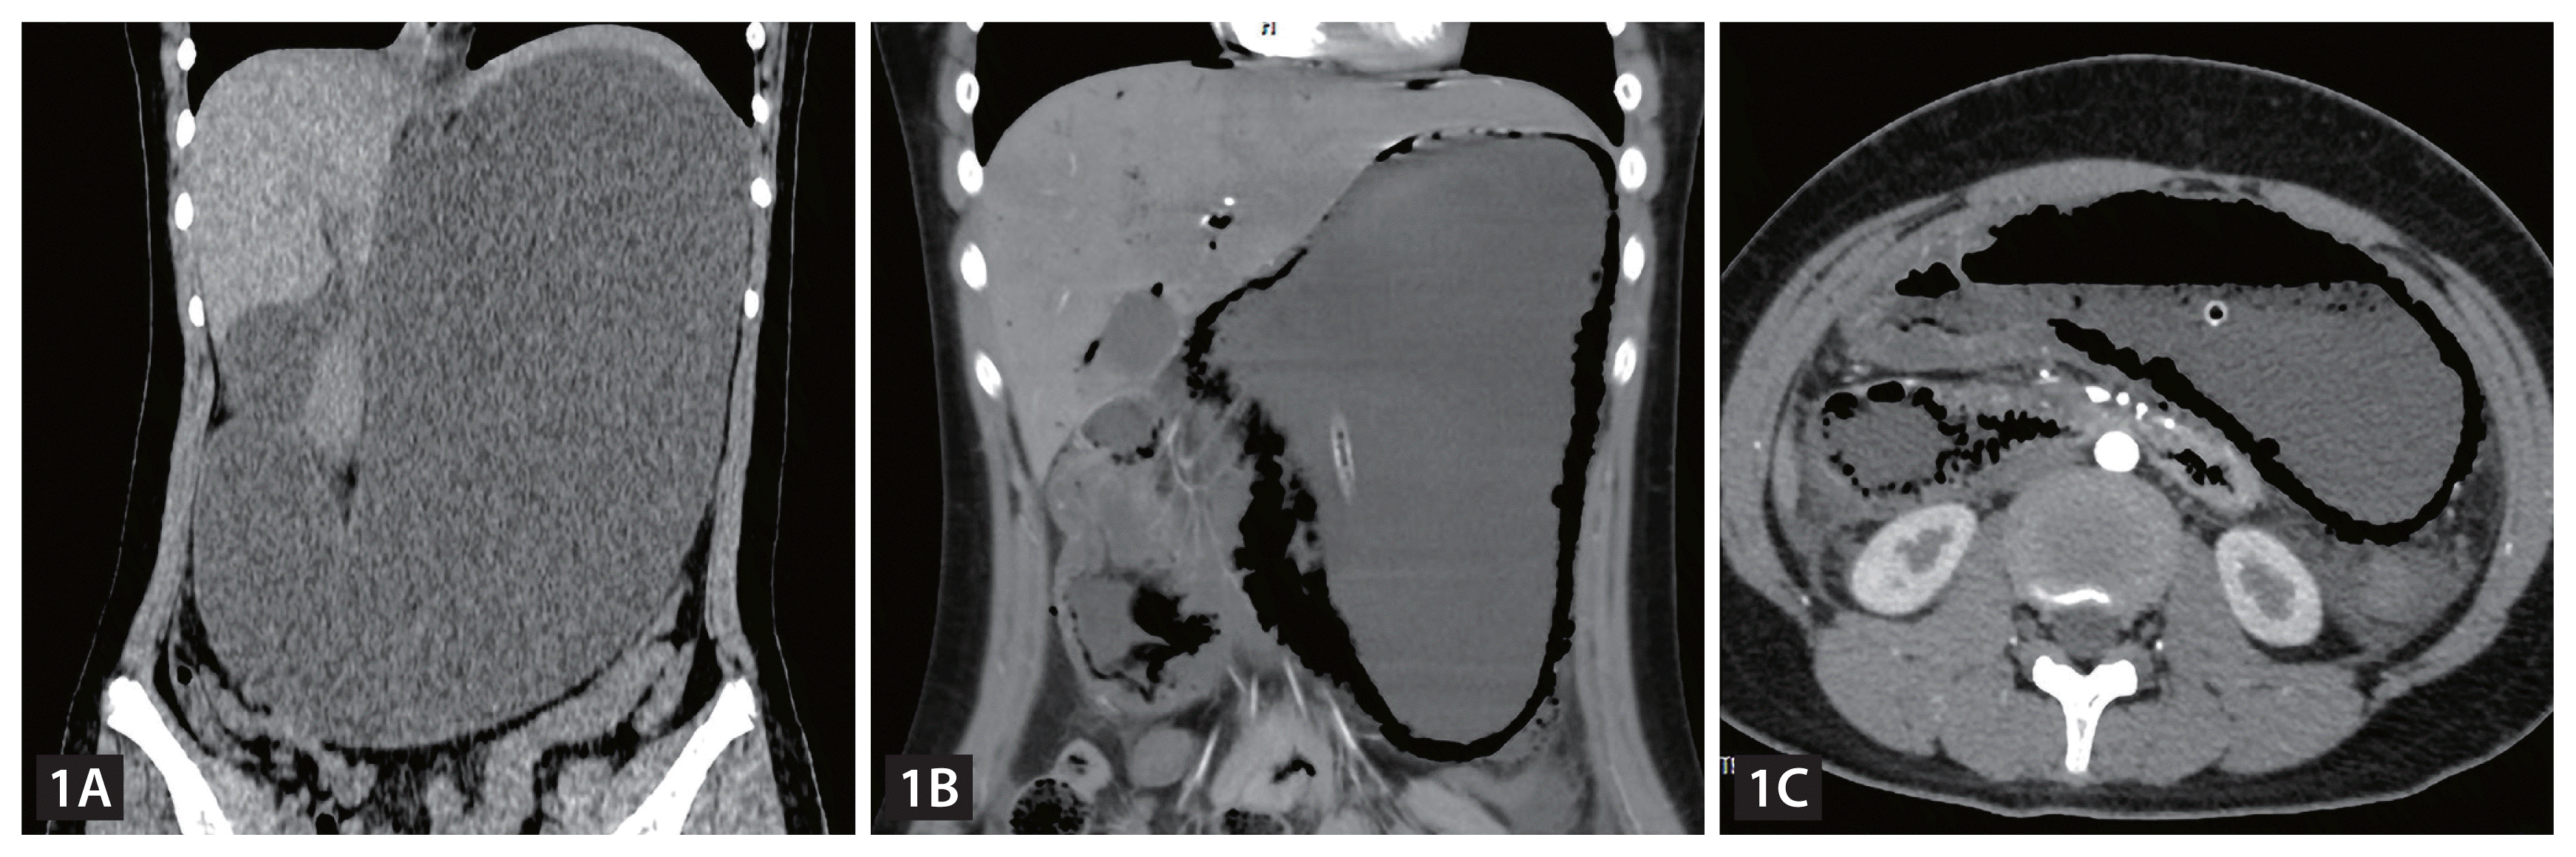

A 14-year-old girl presented to the emergency department with severe abdominal pain. To celebrate her success with school exams, she had a history of binge eating. A non-enhanced computed tomography (CT) scan showed marked dilatation of the stomach (Fig. 1A). After 10 hours, an enhanced CT showed extensive pneumatosis of the gastroduodenal wall and intrahepatic portal vein (Fig. 1B). In addition, we found that the superior mesenteric artery aggravated the degree of duodenal obstruction (Fig. 1C), and the angle between the superior mesenteric artery and the abdominal aorta was sharply decreased (Fig. 2A, B). Meanwhile, the laboratory inspection found a white blood cell count of approximately 38.80 × 109/L and a NEU count of approximately 35.58 × 109/L. An emergency operation revealed that approximately 2/3 of the gastric wall tissue was widely blackened and necrotic (Fig. 2C). The patient eventually underwent a proximal subtotal gastrectomy. Fortunately, the patient improved and was discharged after 2 months.

Figure 1

Massive gastric dilatation. (A) Extensive pneumatosis of the gastroduodenal wall and intrahepatic portal vein. (B) The superior mesenteric artery aggravated the degree of duodenal obstruction (C).